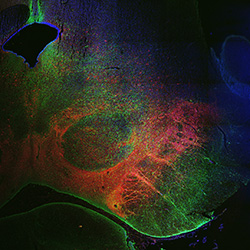

An anatomical analysis of the developing human midbrain from 6 post-conceptional weeks (PCW) to 22 PCW reveals increased tissue complexity, characterized by the emergence of dopaminergic nuclei, as highlighted by immunofluorescence analysis for tyrosine hydroxylase (TH).

7PCW

DAPI

7PCW human midbrain

MAP2

TH

Merged